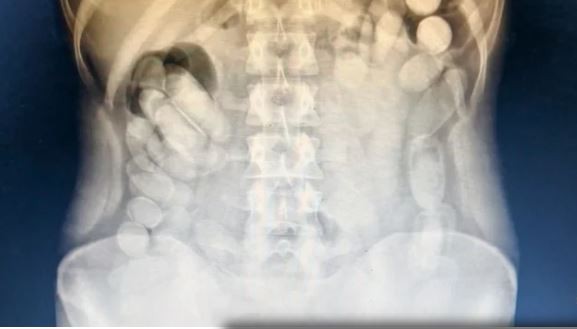

Una vez en el Nosocomio local, se le realizó una radiografía a la mujer mediante la cual se pudo observar la presencia de las dosis en su abdomen. Más tarde, la involucrada evacuó 106 cápsulas.